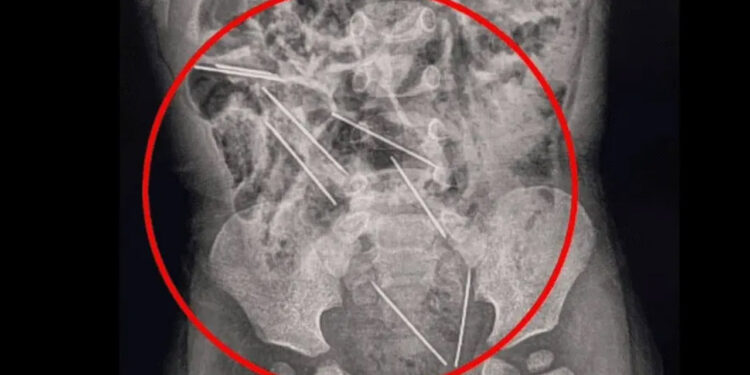

Al llegar al hospital la madre informó de lo sucedido a los médicos y éstos intervinieron rápido para ayudarlo, donde lo primero que hicieron fue sacarle una radiografía para determinar dónde estaban las agujas.

Luego de la radiografía los médicos notaron que algunas de estas agujas se encontraban muy cerca de los órganos vitales del bebé, por lo que tuvieron que someterlo a cirugía casi de forma inmediata debido al riesgo que estas representaban.

Pasaron cerca de dos horas desde que inició la intervención quirúrgica en el menor y los médicos lograron retirar las agujas del cuerpo del niño, y una alcanzó a hacer una lesión leve en el intestino delgado del menor.